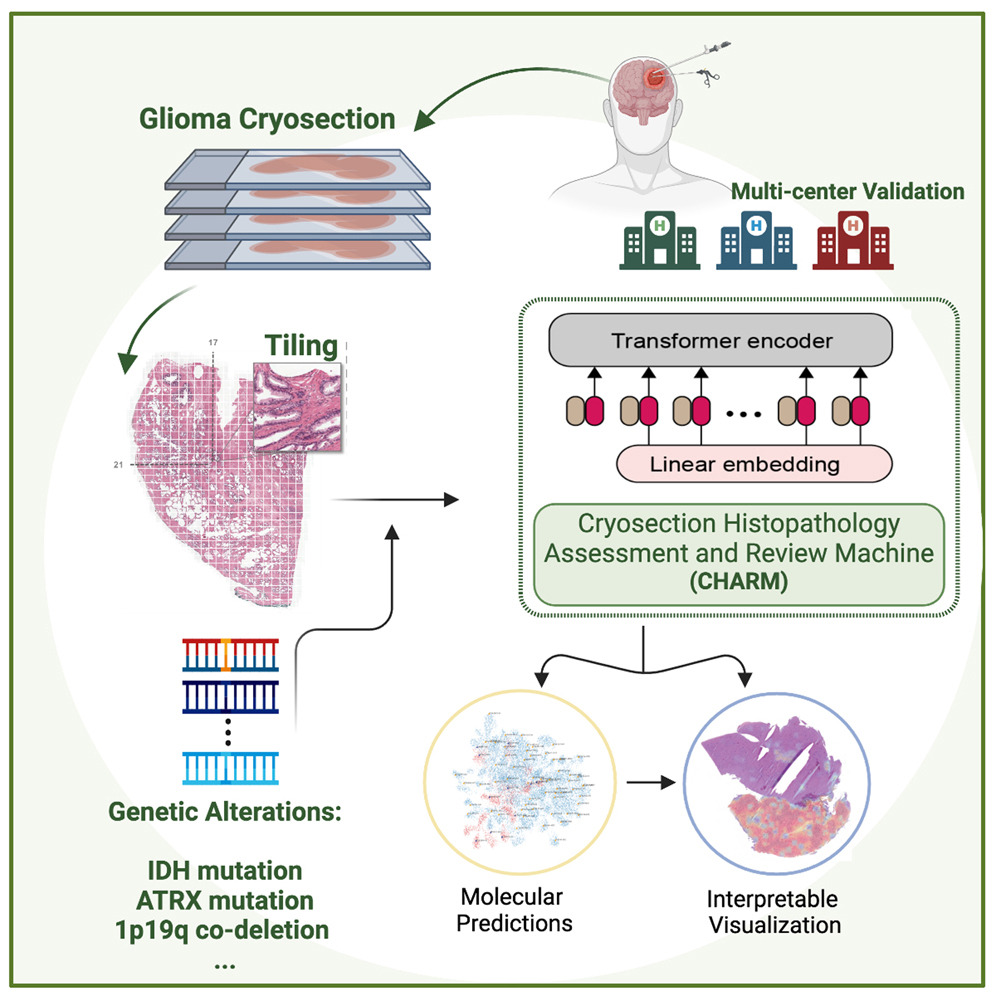

Il tool AI in questione è denominato CHARM (Cryosection Histopathology Assessment and Review Machine), è disponibile gratuitamente per altri ricercatori ma prima di poter essere implementato nelle strutture ospedaliere deve ancora essere clinicamente validato secondo protocolli specifici e ottenere il via libera dalla Food and Drug Administration (FDA), l’agenzia governativa statunitense che si occupa della regolamentazione dei prodotti alimentari e farmaceutici.

CHARM è stato sviluppato partendo da 2334 campioni di tumori cerebrali di 1524 persone con glioma (un tumore cerebrale aggressivo), di tre differenti popolazioni di pazienti. Testato su un campione inedito di campione di tessuto cerebrale, il tool è stato in grado di distinguere tumori con specifiche mutazioni molecolari, con il 93% di precisione, e classificare correttamente tre tipi di gliomi, distinguendo caratteristiche molecolari che comportano differenti prognosi e conseguenti trattamenti.